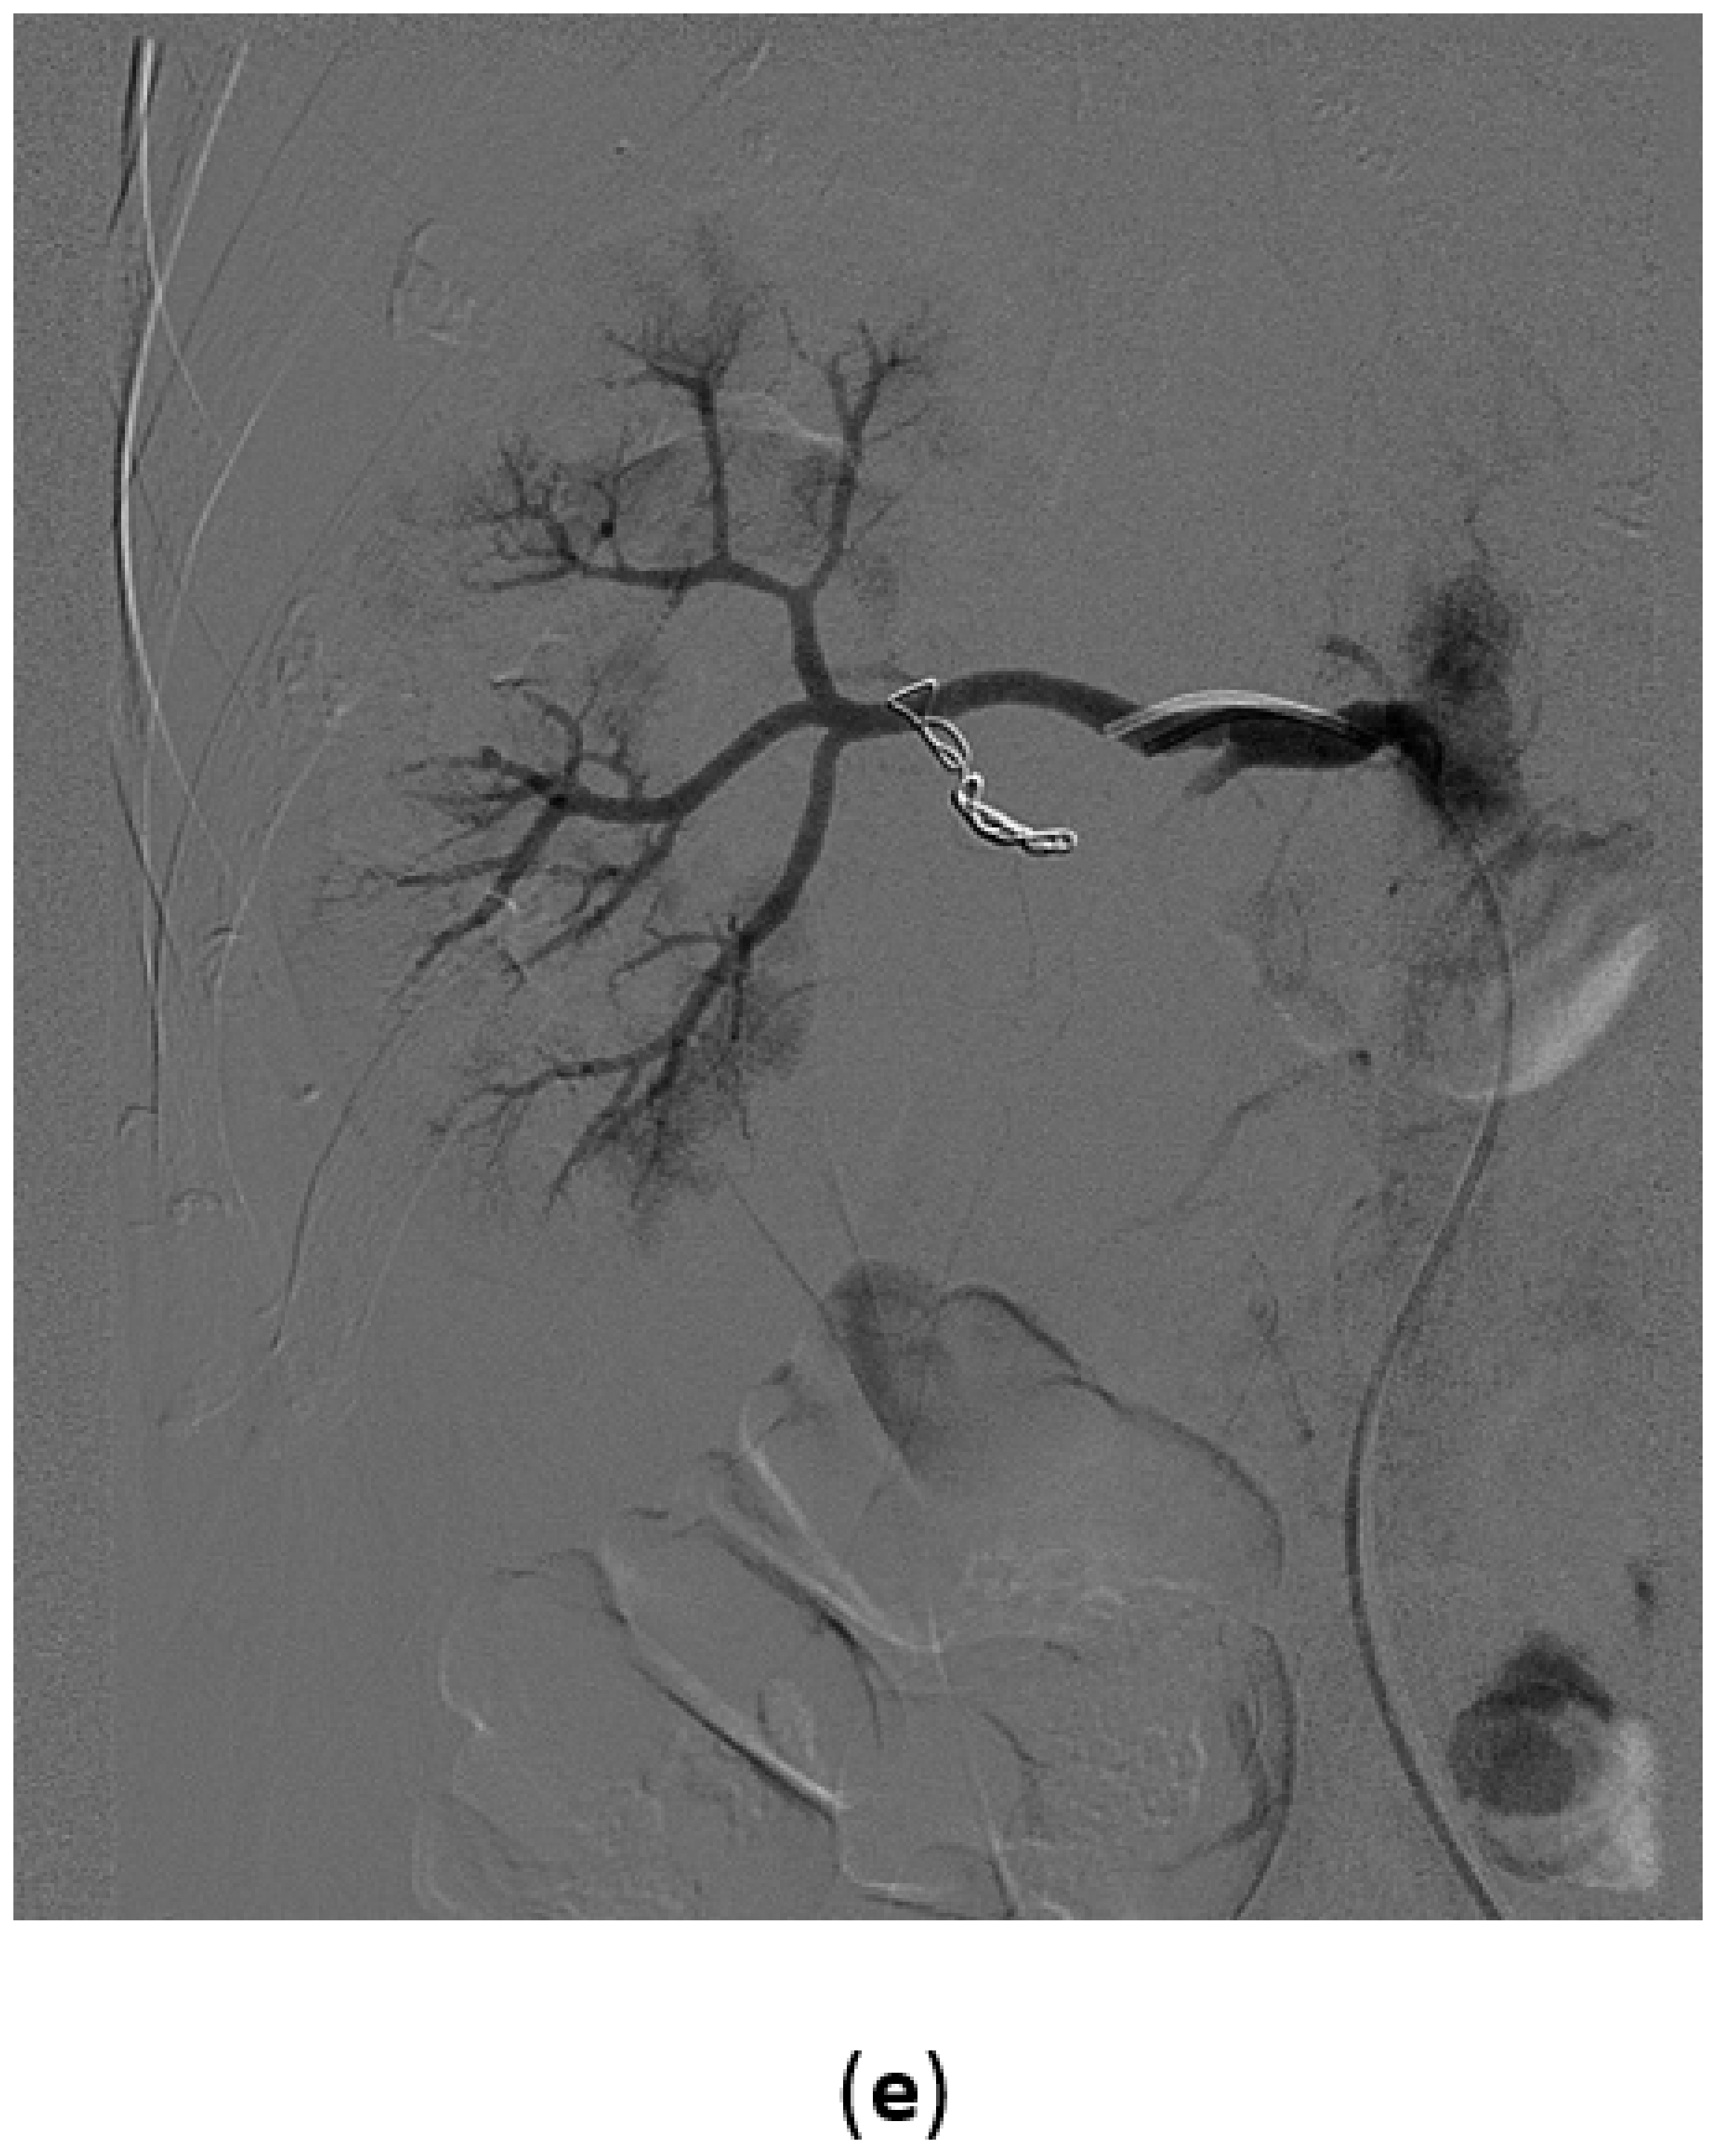

3.2. Renal Artery Pseudoaneurysm (RAP)

3.3. Renal Arterovenous Fistula (AVF)